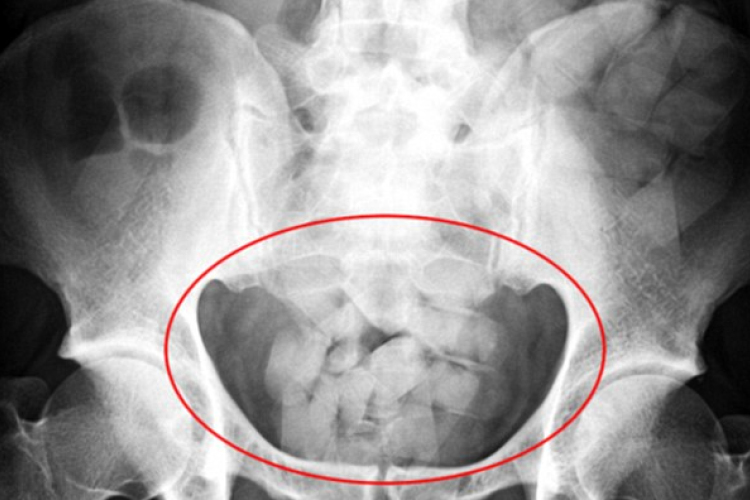

Testében csempészte az 50 millió forintnyi kokaint

Elfogták azt a brazil férfit a budapesti felderítők, aki 90 kokain kapszulát csempészett Dél-Amerikából Magyarországra.